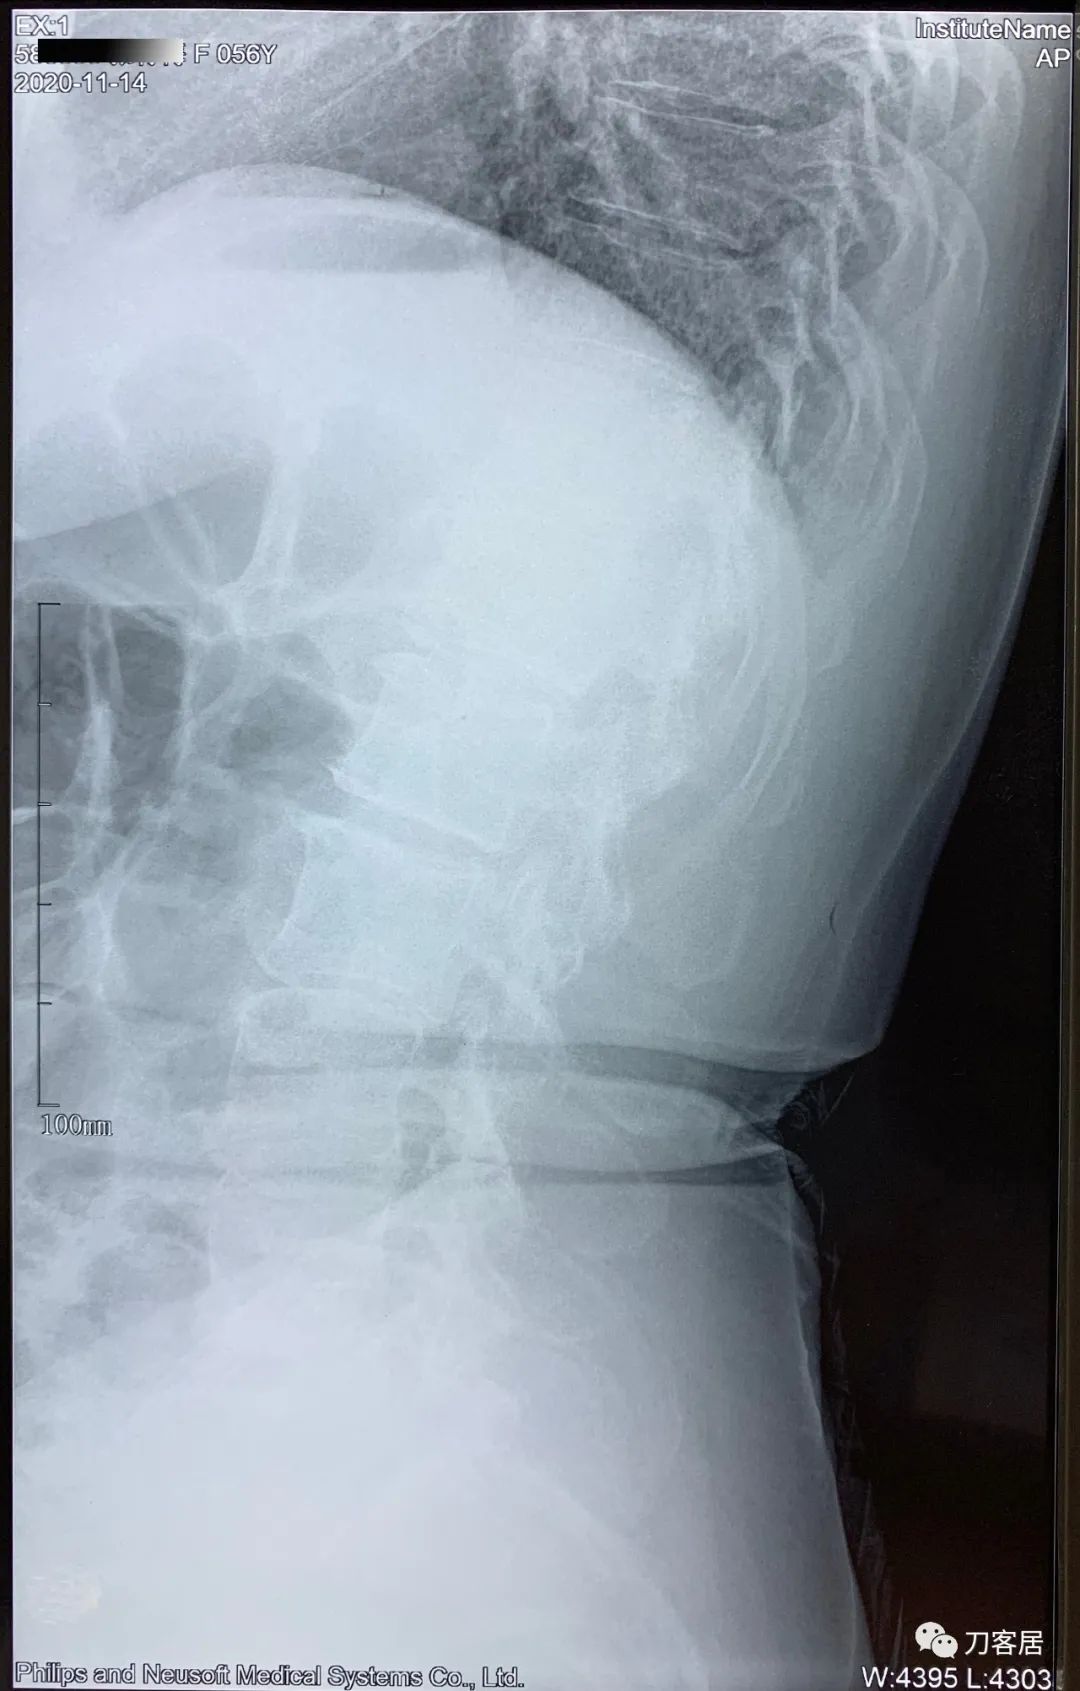

2021年5月17日,西京医院骨科门诊找我就诊,自带影像学检查资料提示腰椎侧弯,腰3-4,腰4-5椎间盘突出,黄韧带肥厚,椎管狭窄。

建议其查双光子骨密度,骨盆正位片以及腰椎间盘平扫。腰椎正侧位X线片以及动力位片,站立位脊柱全长正侧位X线片,以了解其是否有骨质疏松,并了解脊柱侧弯情况,腰椎局部X线表现情况和腰椎间盘突出和椎管狭窄情况。

从这个患者的影像资料分析,颈椎间盘突出问题不大,没有明确的上位神经元损伤表现,所以,不考虑颈椎和胸椎问题。腰椎侧弯畸形,但不严重。因为存在腰椎侧弯,使得腰椎MRI在扫描切面的时候,显示的椎间盘突出或椎管狭窄会有一定的误差,所以,又加做了经椎间盘的CT平扫,影像表现并不严重,综上,腰椎间盘突出,腰椎管狭窄,腰椎侧弯,不考虑手术治疗。同时,患者的主要痛苦是心理疾病,而不是器质性疾病,所以,以心身疾病治疗为主。虽然患者骨密度检查结果提示正常,但X线片显示骨质疏松,且其症状也与骨质疏松的症状有符合之处,比如静息痛,不能入睡,动作及姿势变换时痛加重等,所以,给予实验性抗骨质疏松治疗,以观疗效。